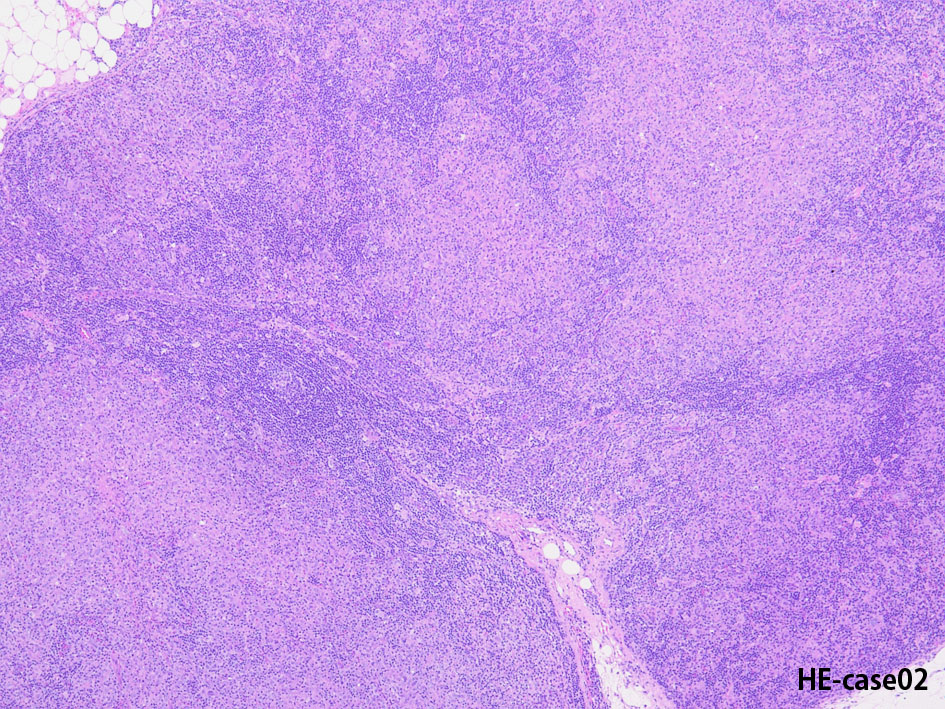

Hodgkin lymphoma-Case02-IWT

74歳男性 左頚部リンパ節腫大

組織球が類上皮細胞様に集蔟して肉芽腫様病変を形成, リンパ節内に明るく見えるエリアができている。HRS細胞が散在。背景はリンパ球, 形質細胞。好酸球が多く見られる